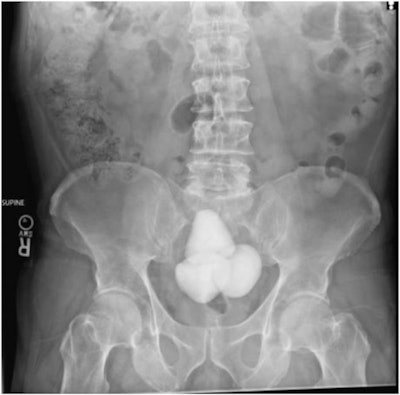

According to the report, the patient had known bladder obstruction due to enlarged prostate and presented with difficulty performing intermittent catheterization due to pain. A subsequent kidney, ureter, and bladder x-ray revealed 13 centimeters of conglomerated radiopaque bladder stones. On review of imaging, the "impressive bladder stones" were conspicuously absent on x-ray 32 months prior, the authors noted.

A KUB (kidney, ureter, and bladder) x-ray showing gigantic bladder calculi in a 60-year-old patient with known chronic urinary retention. Image and caption courtesy of Urology Case Reports through CC BY 4.0.In addition, a nuclear medicine sestamibi parathyroid scan demonstrated increased radiotracer uptake within the right inferior parathyroid gland, confirming a diagnosis of primary hyperparathyroidism, the group noted.